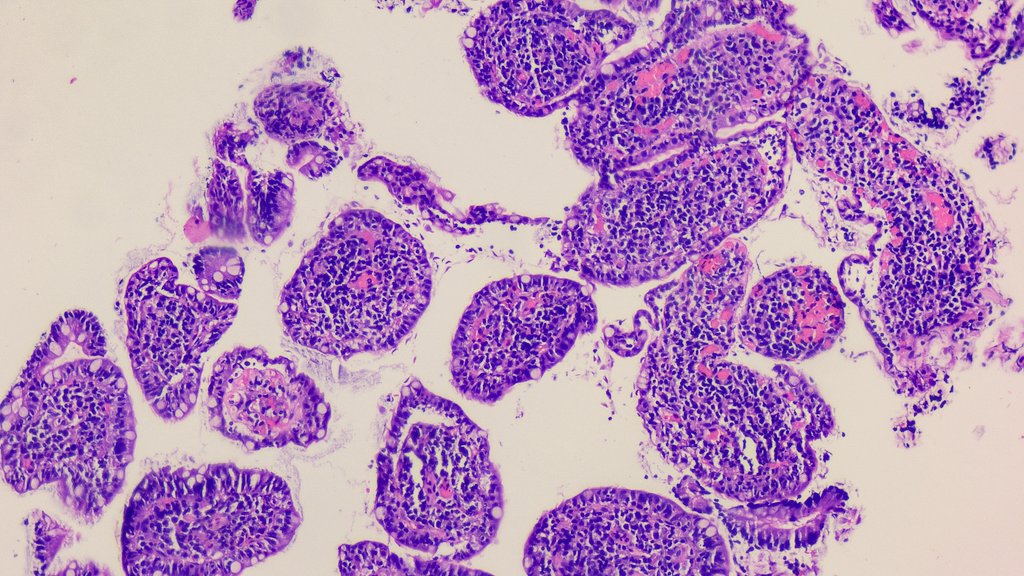

Nasal mass in young male #ENTPath #PathX What is your differential diagnosis? Which stain(s) are confirmatory? @Pathoutlines @UMichPath

MeredithKHerman's tweet image. Nasal mass in young male #ENTPath #PathX

What is your differential diagnosis?

Which stain(s) are confirmatory?